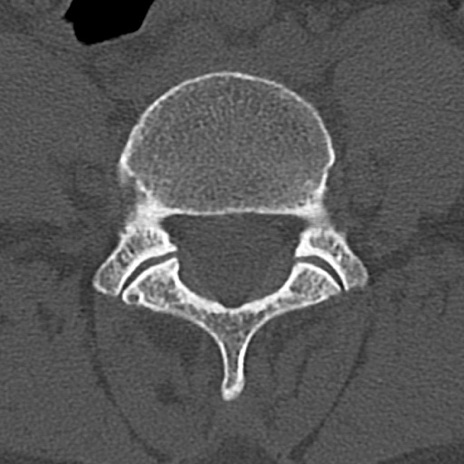

腰椎CT

横断像と矢状断像